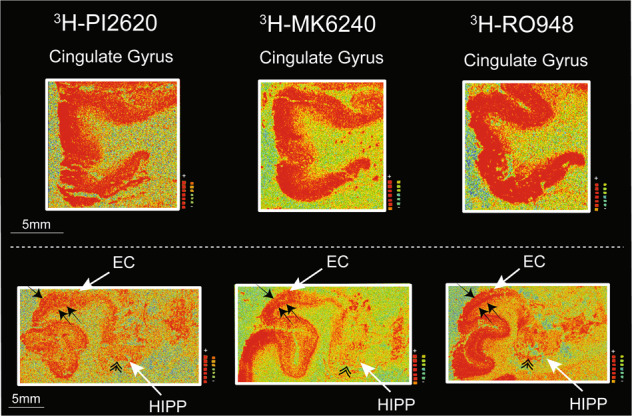

3H-PI2620, 3H-MK6240 and 3H-RO948 autoradiography binding comparison in different layers of distinct cortical regions on large frozen adjacent hemispherical brain sections from a patient with sporadic AD

In cingulate gyrus, where the layer 4 of the cortex is absent, all three tau tracers bound strongly throughout all layers (Fig. 4; top panel). Similar qualitative/visual assessment in the entorhinal cortex (EC), showed high binding of 3H-MK6240 and 3H-RO948 in all layers; with a specifically stronger binding in the deep layers (Fig.4; lower panel, small double arrows). The 3H-PI2620 binding was less intense and more diffuse in all EC layers (Fig. 4; lower panel). Moreover, using 3H-PI2620, the discrimination between binding in superficial (small single arrow) and deep layers (double single arrows) was very subtle/non-existent compared to 3H-MK6240 and 3H-RO948 binding, where a clear distinction was observed between superficial and deep layers (Fig. 4; lower panel). Similarly, in the hippocampal (HIPP) CA1 region (double arrowhead), 3H-PI2620 demonstrated qualitatively less binding than 3H-MK6240 and 3H-RO948 (Fig. 4; lower panel).

We also compared the binding properties of 3H-PI2620 with those of other 3R/4R tau tracers in the FC of AD brains, as in our earlier studies with MK6240 in the same AD patients’ brains [ref. 21]. Unlabelled RO948 competed for two binding sites with analogous affinities and, as before, our competitive studies between 3H-PI2620 and unlabelled MK6240 revealed two binding sites with affinities similar to those of unlabelled PI2620. Interestingly, in addition to the similar affinities for the three tau tracers in AD brains, the proportions of SHA and HA binding sites were also similar for the three tracers (the HA site accounted for more than 70% of the sites), stressing their similar binding behaviour in AD brains, rich in 3R and 4R isoforms. In our previous study, we showed that 3H-MK6240 had equivalent affinity (Kd = 0.3 nM) in the TC of AD brains [ref. 21]. Autoradiography of large frozen adjacent hemispherical brain sections from a sporadic AD case corroborated these results. 3H-PI2620, 3H-MK6240 and 3H-RO948 demonstrated the same binding pattern (visually/qualitatively) in the frontal and temporal lobes (neocortex) but a different binding pattern in the hippocampus and entorhinal cortex (allocortex). The three PET tracers all showed similar laminar patterns in the frontal and temporal lobes, with a higher binding intensity in the deeper cortical layers. Similar laminar distribution binding pattern was observed with the tau PET tracer THK5117 [ref. 35].

Interestingly, hippocampal CA1 region and entorhinal cortex displayed less 3H-PI2620 binding than 3H-MK6240 and 3H-RO948 despite the fact that tau tangles should dominate in these regions. The distinct morphological features of very advanced tau pathology in the hippocampus CA1 and entorhinal cortex [ref. 49] might explain the differences in binding properties between the tracers in these regions.